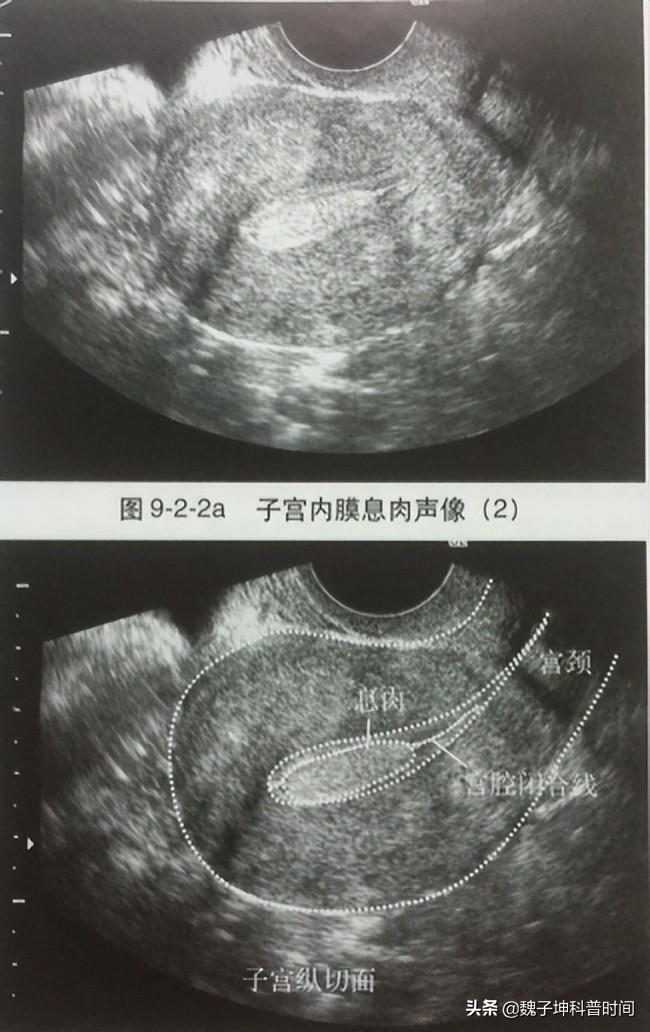

所谓宫腔镜检查,通俗理解就是通过一条细小镜子伸入到宫腔内观察病变的诊断方法。与超声和核磁共振检查相比,其优势就是直接走进了宫腔内进行观察,所获信息由猜测变为确定、由模糊变为清晰、具体,优势无可替代。我们来看一组对比,图1为B超下的子宫内膜息肉,图2为宫腔镜下的子宫内膜息肉,即使不学医的朋友也能看出来宫腔内长了多余的东西。

图1

图2